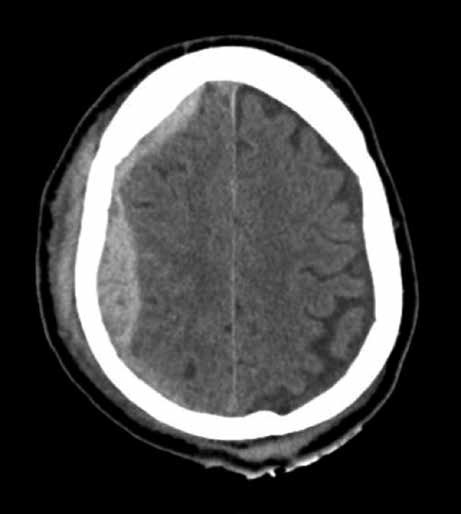

53 – R.M., masculino, 58 anos, etilista, sofre queda de

aproximadamente 6 degraus na escada de sua residência. Chega ao pronto-socorro trazido por familiares com Glasgow = 13 (abertura ocular ao chamado e confuso/desorientado) e hemiparesia desproporcionada incompleta contralateral ao local da sua lesão intracraniana. Realizou imediatamente tomografia computadorizada de crânio sem contraste.

Qual é a lesão que mais destaca-se na região parietal direita do corte tomográfico acima?

a) Hematoma epidural.

b) Hematoma subdural.

c) Hemorragia subaracnóidea.

d) Não há lesão na região parietal direita.

Na tomografia computadorizada de crânio observamos imagem biconvexa e hiperdensa, o que nos fala a favor de hematoma epidural à direita (setas vermelhas); além disso, identificamos a presença de extenso hematoma subgaleal (coleção de sangue entre a tábua óssea do crânio e o couro cabeludo), uma lesão que não traz risco ao paciente (setas azuis). Devemos lembrar que, classicamente, o hematoma epidural se desenvolve devido à lesão na

artéria meníngea média, e mais raramente tem origem venosa. Embora nosso paciente se apresente com escala de coma de Glasgow de 13 (Trauma Cranioencefálico [TCE] leve ou menor), ele está francamente sintomático, com confusão mental e hemiparesia contralateral (não é descrito o estado de suas pupilas), alterações que já podem ser encaradas como sinais de deterioração neurológica. Nesse caso, a intervenção neurocirúrgica deve ser imediata, com craniotomia e evacuação do hematoma. Nos hematomas epidurais, pode haver em até 47% dos casos cirúrgicos (que representam a maioria) o intervalo lúcido antes da deterioração neurológica. Contudo, não observamos este fenômeno em nosso

paciente. Reparem que ele já se apresenta confuso,

desorientado e com sinais motores.